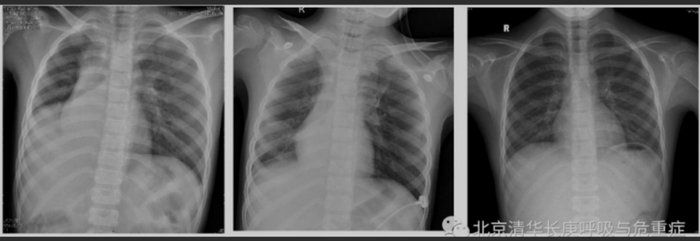

“临床建议”展示了牟向东团队的救治实例。一名8岁女童因进行咳嗽、发热、呼吸困难3天而入院,指尖血氧饱和度88%左右,心率135次/分。入院当日的胸片正位显示右下肺不张,气管及纵隔向右移位。后经反复吸痰、支气管冲洗及肺泡灌洗,患者氧饱和度逐渐恢复正常;其后复查胸片逐渐恢复正常。

图源:清华长庚医院呼吸与危重症医学科